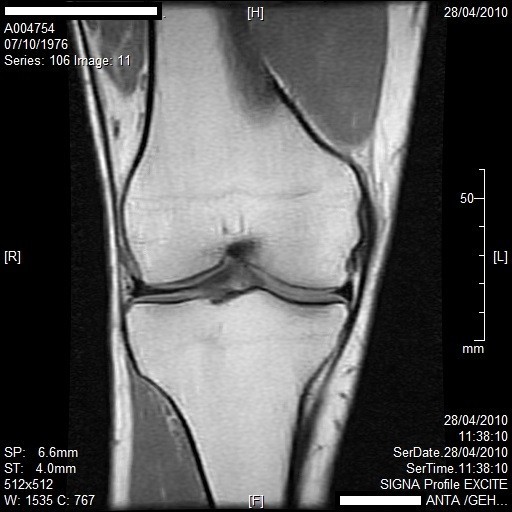

La resonancia magnética combina la tecnología de la computación, un campo magnético y ondas de radio para producir una imagen bidimensional de un “corte” de la anatomía del paciente. Este procedimiento no expone al paciente a radiaciones y las ondas de radio son inofensivas.

A diferencia de los barridos de la Tomografía Computada y las imágenes de rayos X, la resonancia magnética produce imágenes altamente detalladas que son aptas para la identificación de patologías de los tejidos blandos. Otra ventaja de la resonancia magnética es que puede producir imágenes de diferentes planos anatómicos, por lo que hace posible el estudio de la anatomía desde diferentes ángulos.